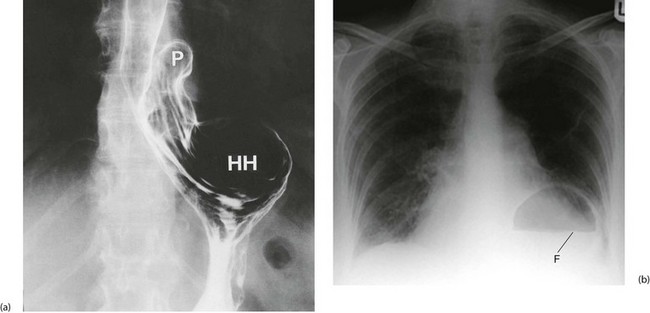

Hiatus hernia occurs when the proximal part of the stomach passes through the diaphragmatic hiatus up into the chest (see Fig. 22.5). Around 90% of hiatus hernias are of the sliding type, in which the gastro-oesophageal junction is drawn up into the chest and a segment of stomach becomes constricted at the diaphragmatic hiatus. The hernia tends to slide up into the chest with each peristaltic contraction. These hernias may become huge and, rarely, may contain the whole stomach including pylorus and first part of the duodenum, sometimes with part of the colon as well. In the 10% of non-sliding cases, the gastro-oesophageal junction remains below the diaphragm and a bulge of stomach herniates through the hiatus beside the oesophagus. These are described as para-oesophageal or rolling hiatus hernias.

Fig. 22.5 Types of hiatus hernia

(a) Sliding hiatus hernia, which is common. This type disrupts the physiological anti-reflux mechanism. (b) Rolling or para-oesophageal hiatus hernia, which is rare. The anti-reflux mechanism is usually left intact

In sliding hiatus hernia, the lower oesophageal sphincter mechanism often becomes defective, causing reflux of acid–peptic stomach contents. This is not a problem with rolling hiatus hernias which more usually present with pain or dysphagia.